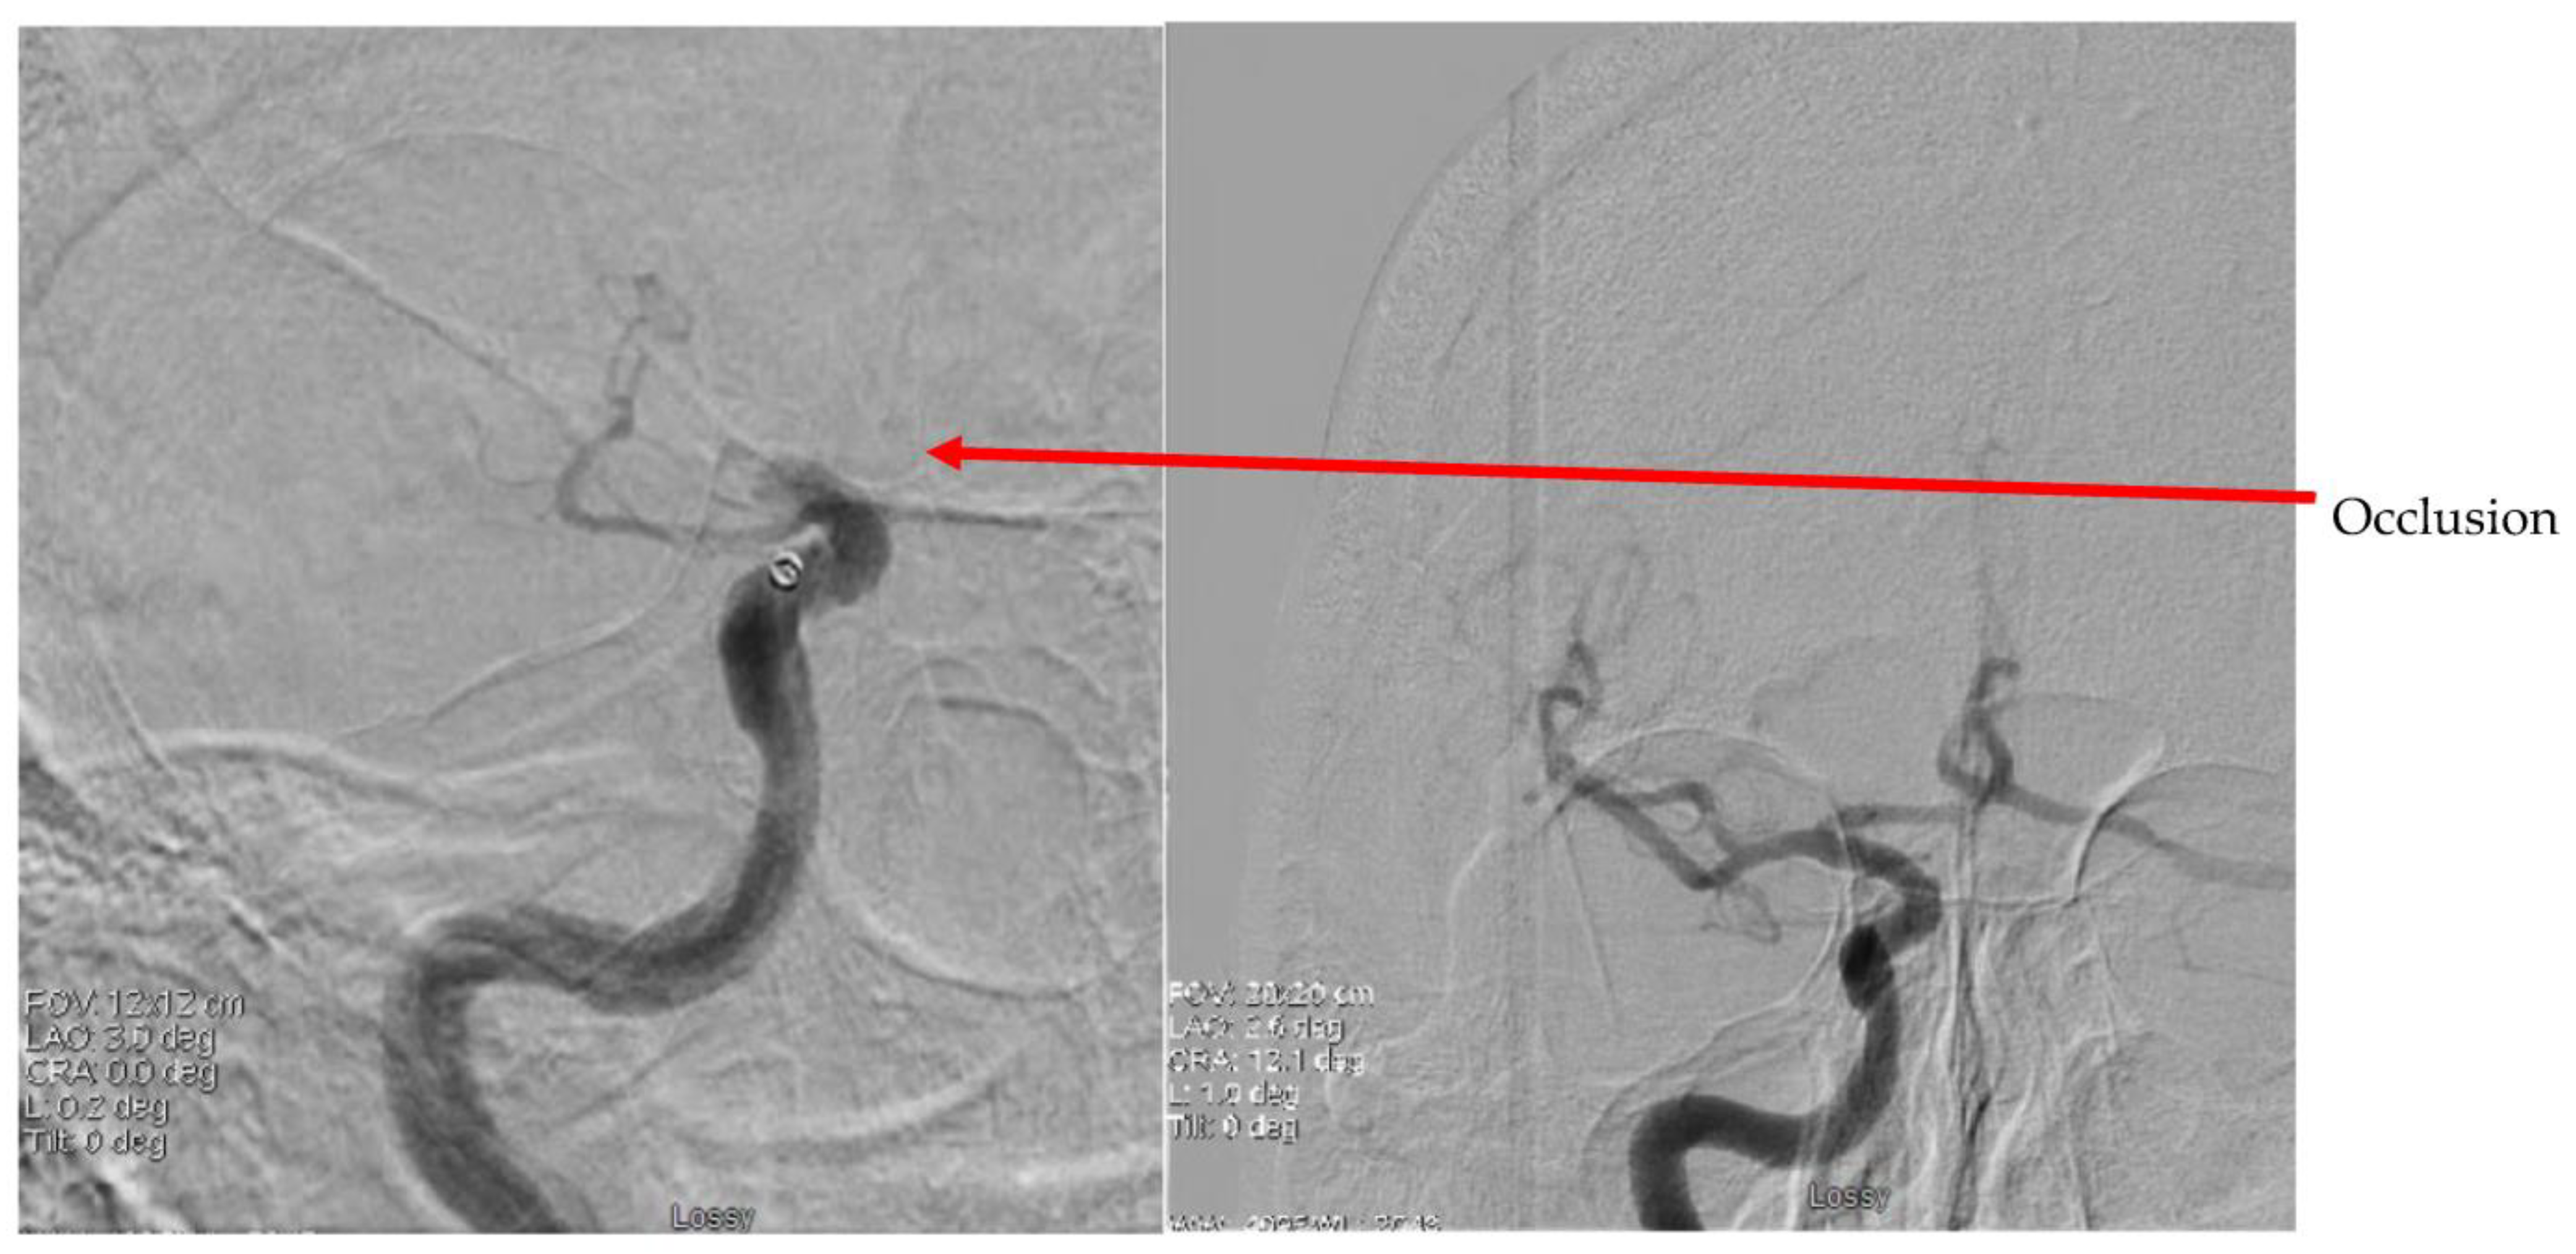

2. Case